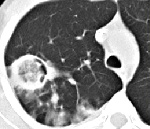

Визуализация и диагностика неинвазивного аспергиллеза с помощью КТ

Раздел: Необычные решения